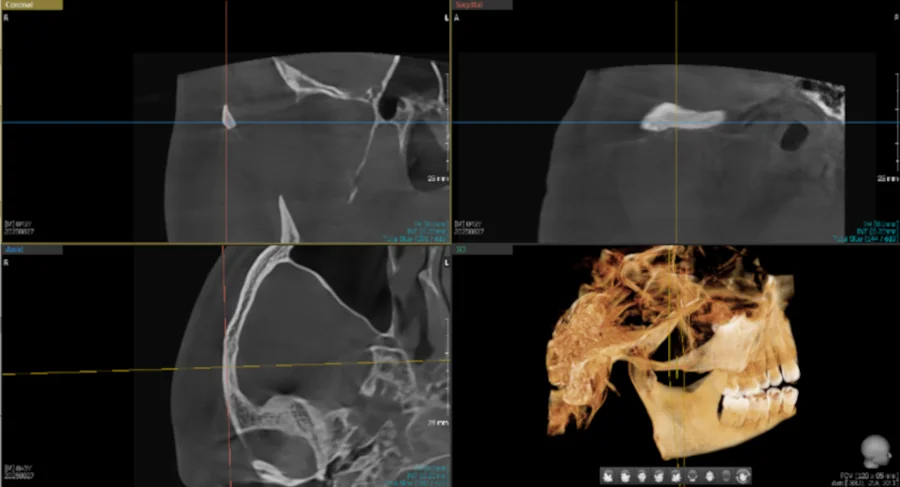

CBCT (Cone Beam Computed Tomography) takes dental imaging to another level. Instead of flat, two-dimensional images, CBCT creates a complete 3D reconstruction of your teeth, jaw bone, nerves, sinuses, and TMJ joints—all in a single scan.

Think of it as GPS for dentistry. We can rotate the image, measure bone density, identify nerve pathways, and plan treatments with millimeter precision. Most dental offices don't have this technology in-house, which means patients often need separate appointments at imaging centers. We bring that capability to you.

2D vs. 3D: The difference in diagnostic detail

When We Use CBCT Imaging

Dental Implant Planning

See exact bone height, width, and density. Identify nerve locations. Plan implant angle and depth with precision—reducing surgical time and improving outcomes.

Impacted Wisdom Teeth Evaluation

Visualize tooth position in 3D. Assess proximity to nerves and sinuses. Determine the safest extraction approach before surgery.

Root Canal Assessment

Detect extra canals or unusual anatomy that 2D x-rays miss. Locate fractures or infections. Plan endodontic treatment with confidence.

TMJ & Jaw Joint Analysis

Evaluate joint structure and movement. Assess bone changes or arthritis. Guide treatment for jaw pain or dysfunction.

Orthodontic Planning

Measure airway dimensions. Assess impacted teeth. Plan tooth movement with complete anatomical context.

The scanning process takes about 20-40 seconds. You'll stand or sit still while the scanner rotates once around your head. The radiation dose is a fraction of a medical CT scan—roughly equivalent to a few days of natural background radiation.

Images are available immediately. We'll review them with you on screen, pointing out areas of interest and explaining what we're seeing. This clarity helps you understand your diagnosis and feel confident about recommended treatment.